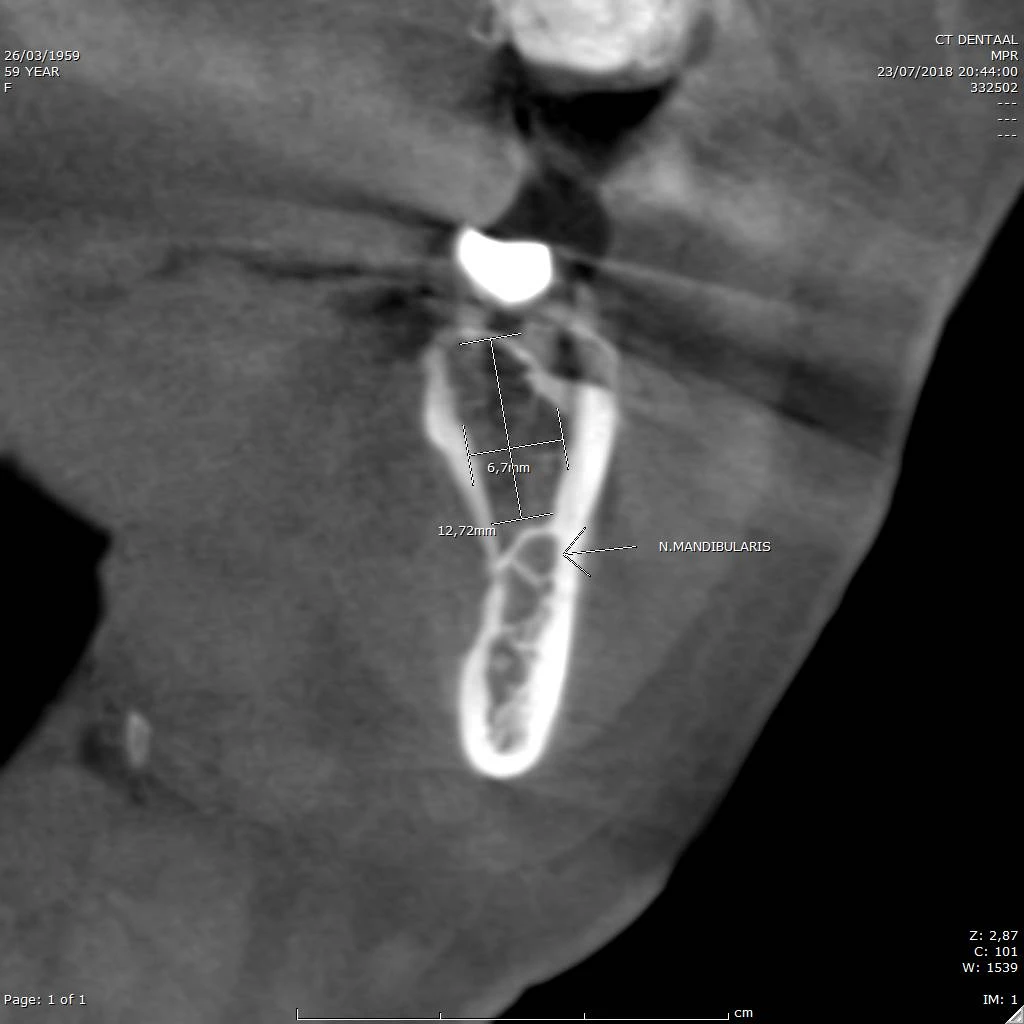

Bepaling bothoogte/breedte voor implant planning. Ligging van de nervus alveolaris inferior (n. mandibularis).

CBCT voorbeeld 9: n. mandibularis en botmetingen

Coronale doorsnede: ligging van de n. mandibularis en botmetingen voor implant planning